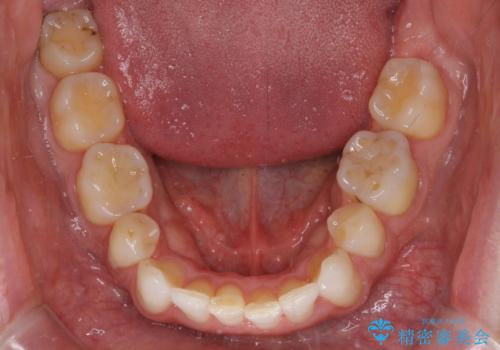

- 上下前歯の叢生を気にして来院された患者様です。

抜歯矯正をした後戻りということで、歯列不正はそれほど大きくなかったため、インビザライン・ライトを用いて矯正治療を行うこととしました。

前歯のデコボコが残っており、シミュレーション通りに動いていない部分がありましたが、再矯正であることやご本人の満足いくところまでデコボコが改善されたとのことで、治療を終了することとしました。